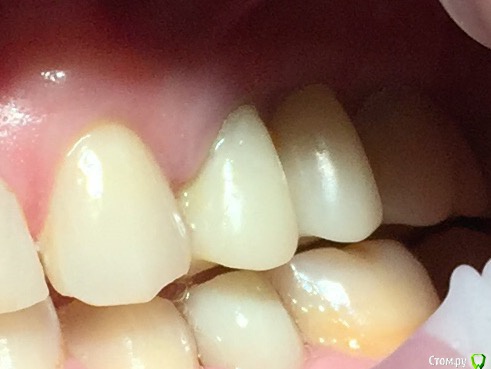

Глеб Митрофанов Опубликовано 12 сентября, 2015 Поделиться Опубликовано 12 сентября, 2015 (изменено) Направлена ортопедом , к которому пришла от другого хирурга и ортопеда , которые оперировали и изготавливали времянки соответственно . Пришла с просьбой - хочу сосочки ! Изменено 12 сентября, 2015 пользователем Глеб Митрофанов Ссылка на комментарий

Глеб Митрофанов Опубликовано 12 сентября, 2015 Автор Поделиться Опубликовано 12 сентября, 2015 А какой вопрос? С какой целью написали?Что возможно сделать , чтоб сделать максимально приближенное к желаемому ? Работа с мягкими тканями , времянками ?? Ссылка на комментарий

faity Опубликовано 12 сентября, 2015 Поделиться Опубликовано 12 сентября, 2015 пластика с бугров наверху, снизу полностью переделывать ортопедию и делать пластику с бугров. Гамборена вчера показывал как))) carlos показывает уже год 4 Ссылка на комментарий

Aquarius Опубликовано 12 сентября, 2015 Поделиться Опубликовано 12 сентября, 2015 Что возможно сделать , чтоб сделать максимально приближенное к желаемому ? Работа с мягкими тканями , времянками ??Если имплант не глушить, то по моему никак Ссылка на комментарий

Mane Опубликовано 12 сентября, 2015 Поделиться Опубликовано 12 сентября, 2015 снимаешь временную коронкупересаживаешь сст с бугра на тонкий формировательждешь месяцоцениваешьпротезируешь 2 Ссылка на комментарий